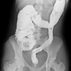

Кишечная непроходимость — состояние, при котором нарушается или прекращается пассаж (продвижение) пищи по кишечнику.

Скручивание кишечника вызывает блокирование пищевого материала и, как правило снизился приток крови к пострадавшим кишечника.